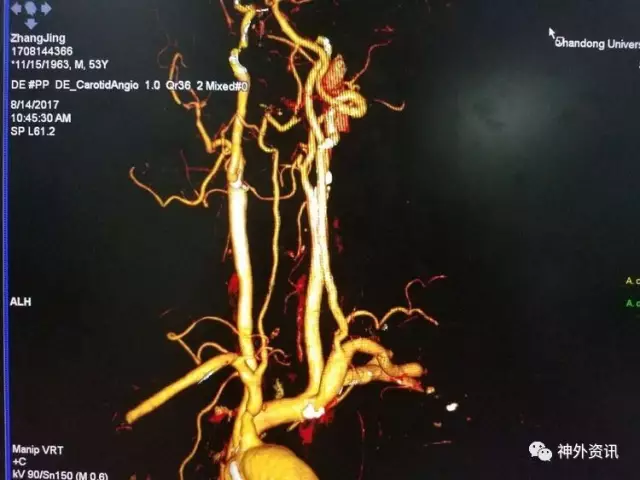

一月后CTA复查,左椎A开口无狭窄,远端管腔变粗,低灌注造成的狭窄明显改善,病人症状完全缓解